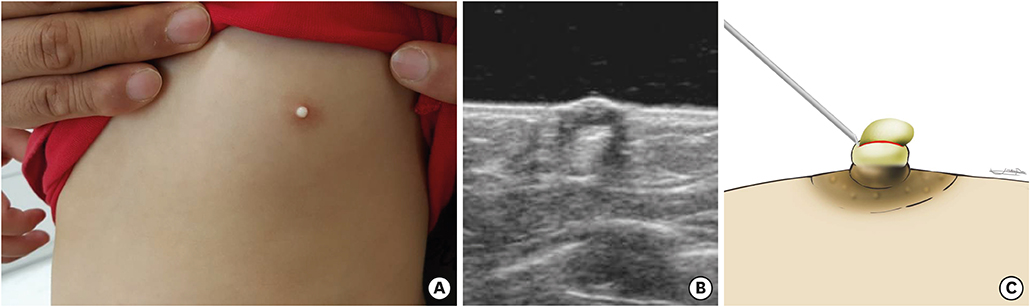

Fig. 1). Pathologic findings were compatible with an epidermal inclusion cyst showing squamous epithelium with lamellated keratinous materials (

Fig. 2). After the first operation, the lesion appeared to be healed with slight elevation of left nipple, However, 16 months later, the patient revisited our hospital due to recurrence in the form of a 4×1.5 mm milk-colored, central elevation of the nipple. Excision of the lesion-containing capsule was performed with a No. 15 surgical blade in the outpatient clinic (

Fig. 2 Pathologic finding: stratified squamous epithelium with lamellated keratinous material.